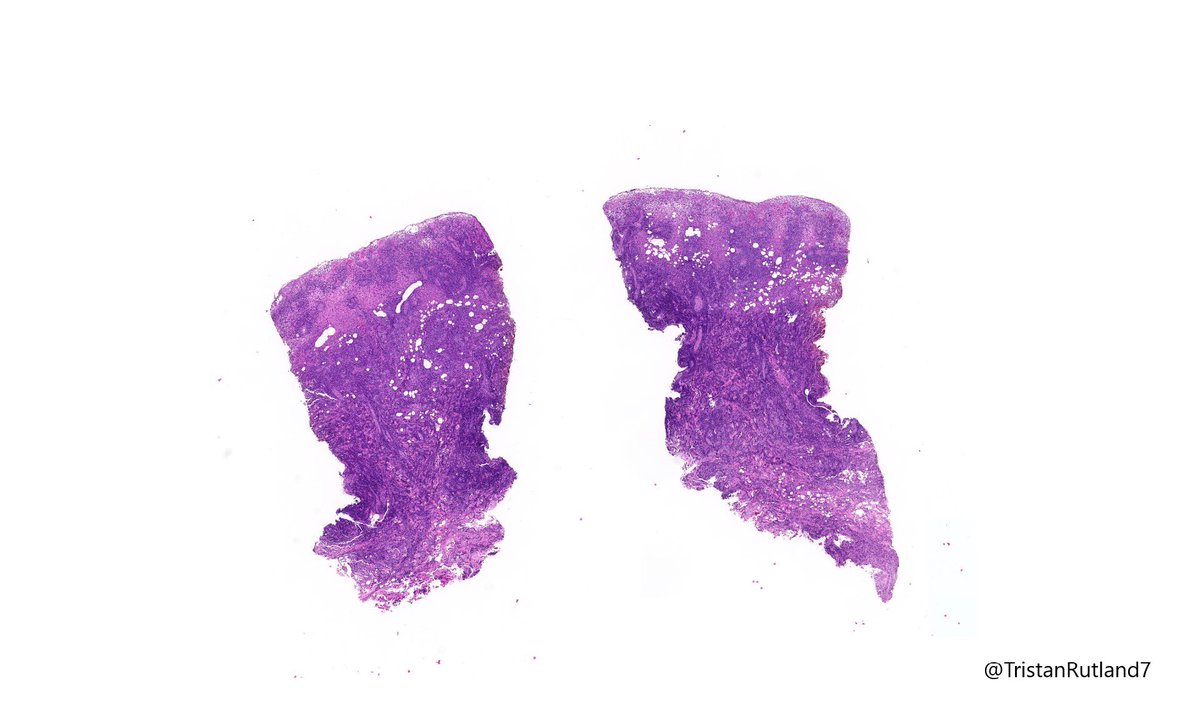

Female, adult, leg.

Large cell transformation of mycosis fungoides (MF).

1/ Mycosis fungoides (MF) is a cutaneous T-cell lymphoma and has a range of stages:

Patch & plaque stage

Tumour stage

3/ Large cell transformation is defined by greater than 25% large cells (4X size normal lymphocytes) or nodular aggregates in dermis.

4/ It usually arises from tumour stage (rare cases arising from patch stage have occurred).